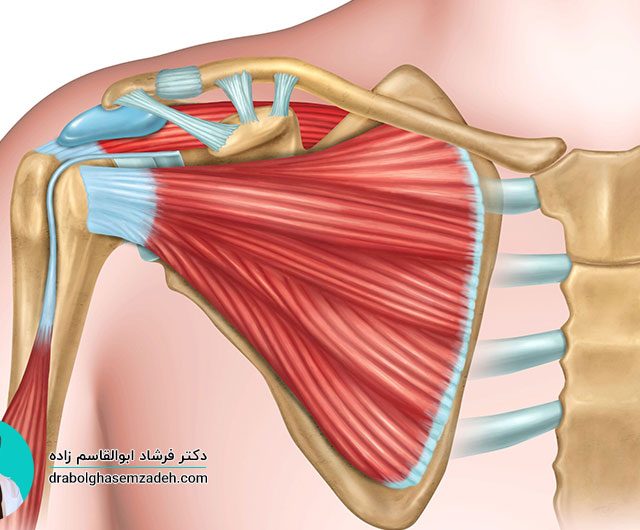

علت درد بازو

بیشتر افراد به هنگام داشتن بازو درد، علت آن را وارد شدن ضربه به آن می دانند. وارد شدن ضربه به بازو، یکی از دلایل درد بازو عنوان شده است؛ اما دلایل دیگری برای احساس درد در بازوها وجود دارند. برای درمان، درد بازو، مهم ترین کار تشخیص علت درد بازو است. علت درد، انتخاب […]...